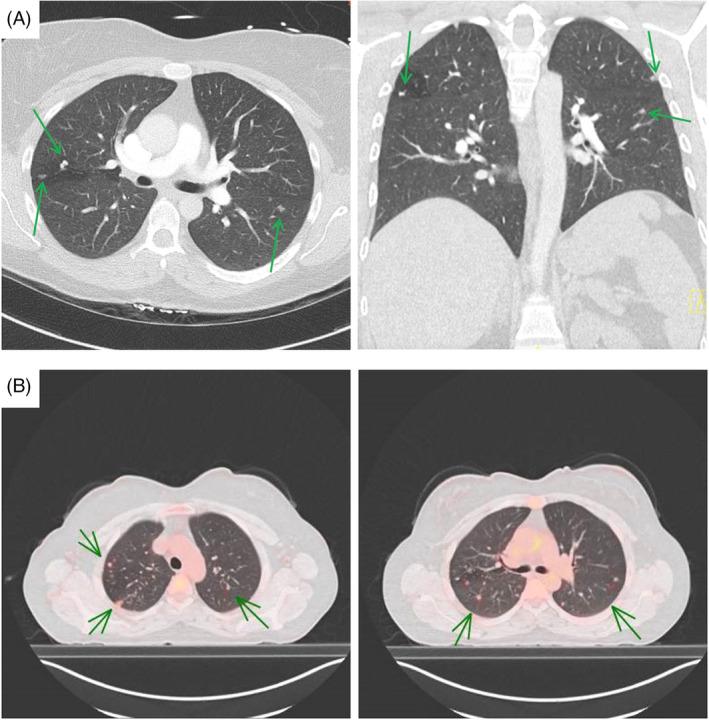

Unravelling diagnostic challenges: A case report of pulmonary langerhans cell histiocytosis with atypical radiologic presentation.

Bronchoalveolar Lavage as a Diagnostic Tool in an Atypical Pulmonary Langerhans Cell Histiocytosis.

Early and Atypical Radiologic Presentations of Pulmonary Langerhans Cell Histiocytosis: A Report of Two Cases.

A case of pulmonary langerhans' cell histiocytosis mimicking hematogenous pulmonary metastases.

Pulmonary Langerhans Cell Histiocytosis Presenting as a Solitary Pulmonary Nodule on a Lung Cancer Screening CT.

Pulmonary Langerhans cell histiocytosis: the many faces of presentation at initial CT scan.

Pulmonary Langerhans cell histiocytosis presenting as a solitary nodule.